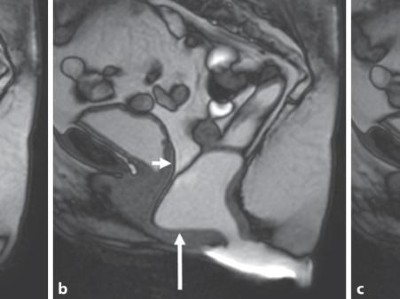

Beckenorganprolaps: Wann operieren, wie rekonstruieren?

Zystozelen, Rektozelen und Enterozelen erfordern eine differenzierte chirurgische Therapie – besonders, wenn konservative Maßnahmen wie Pessare nicht greifen. Eine bebilderte Übersicht über die unterschiedlichen operativen Verfahren und das konkrete chirurgische Vorgehen.